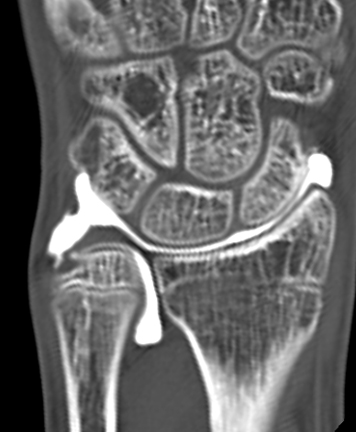

単純X線の他、MRI、手関節造影/CTを行います。単純X線では、TFCC自体は映りません。しかし、骨形態の評価、とくに突き上げ症候群の評価に有用であり、必須の検査の1つです。MRIではTFCCの損傷の有無を評価します。また、ECU腱鞘炎などその他の障害/疾患の有無を確認します。しかしながら、MRIではTFCCの詳細な評価が難しい場合があり、手関節造影/CTが必要となることがあります。手関節造影/CTでは、造影剤を橈骨手根関節内および遠位橈尺関節内に注入しTFCCの円盤部や末梢部、表層部、および小窩(Fovea)部などでの断裂形態を確認します。その他、手根骨間靱帯損傷や手関節尺側部の骨形態について評価します。

【手関節造影後CT】